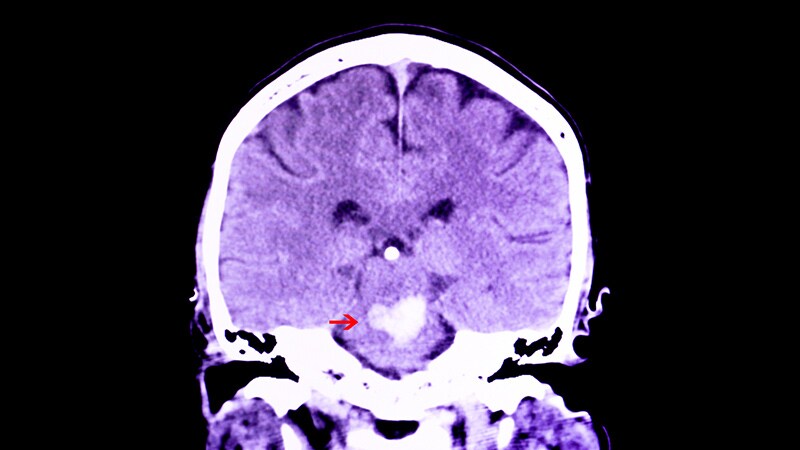

Medscape Medical News, May 23, 2019

Minor Stroke, TIA Diagnosis More Often Missed in WomenDespite presenting with similar symptoms, women were less likely to be diagnosed with an ischemic cerebrovascular event, but

90-day recurrent stroke rates were similar for the two sexes.